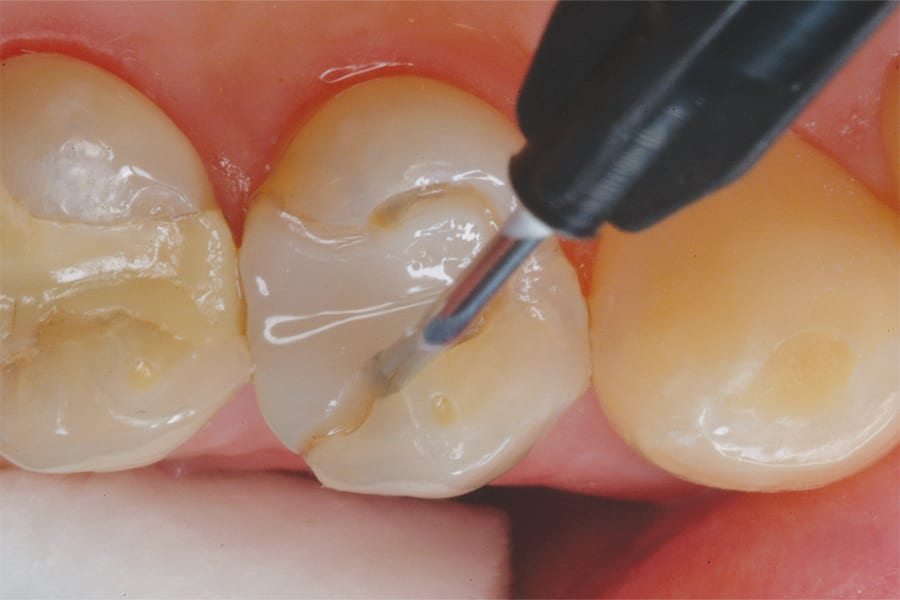

Next, a flowable bioactive nano-hybrid composite (Beautifil® Flow Plus X, Shofu) was placed into the perimeter preparation (Figure 7). It flowed seamlessly into the irregular perimeter, adapting to its complex shape without trapping air bubbles or leaving gaps. This composite was selected for its high strength, resistance to wear, excellent esthetics, and radiopacity. In addition, it features Giomer Technology, which provides healthful benefits by releasing and recharging six beneficial ions, including fluoride. These ions have been clinically proven to inhibit plaque, neutralize acid, and prevent secondary decay.2 Research has shown that Giomer Technology promotes dentin remineralization at the preparation surface adjacent to the restorative.3 Giomer restoratives absorb extra fluoride ions from fluoride-containing products like toothpaste, acting as a reservoir when fluoride is needed in the oral cavity.4,5 Furthermore, Giomer restoratives resist plaque formation due to a film that forms on the surface upon contact with saliva, which inhibits bacterial adhesion.6 All of these characteristics made the selected composite an ideal restorative material for this case. Once the composite was placed, it was light cured per the manufacturer’s instructions.